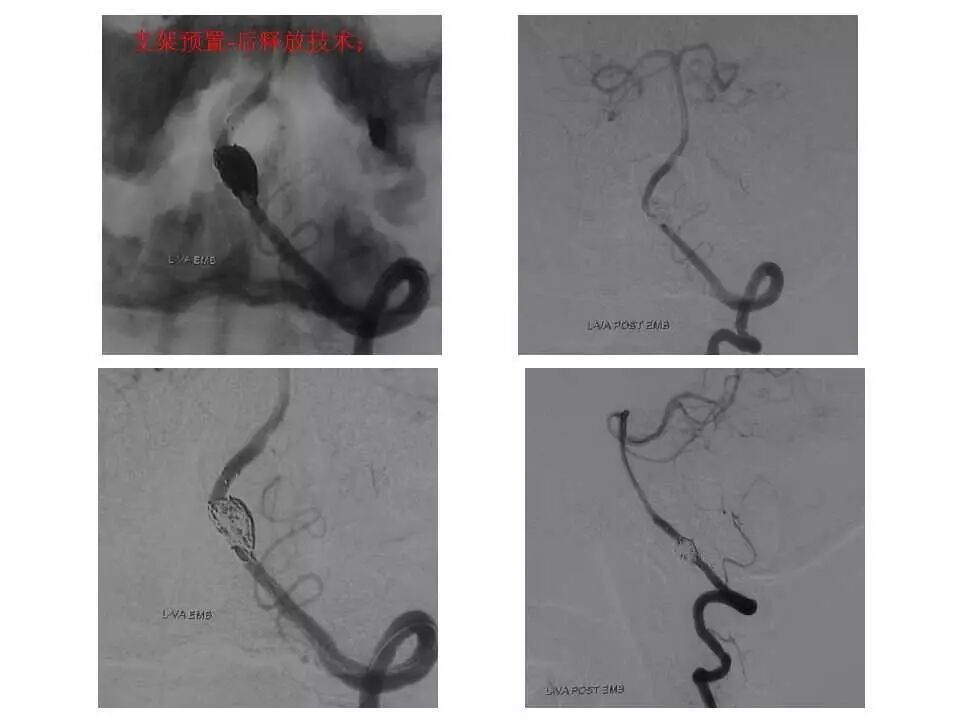

今天为大家分享的是“强生医疗CNV-神经介入专栏”第十五期,由首都医科大学宣武医院何川教授带来的“颅内动脉瘤介入治疗”精彩讲课视频及PPT,欢迎观看、阅读。文章仅代表作者个人观点,如有不同见解,欢迎同道斧正!

何川 ,首都医科大学宣武医院副主任医师,中国医师协会神经介入专业委员会常务委员,长期从事脑血管病和脊髓血管病的手术及介入治疗和相关研究工作。首都医科大学神经外科博士,师从于中国神经介入开创人凌锋教授;日本东北大学医院脑血管病治疗科博士后,师从于日本国脑血管病血管内治疗的开创者高桥教授。